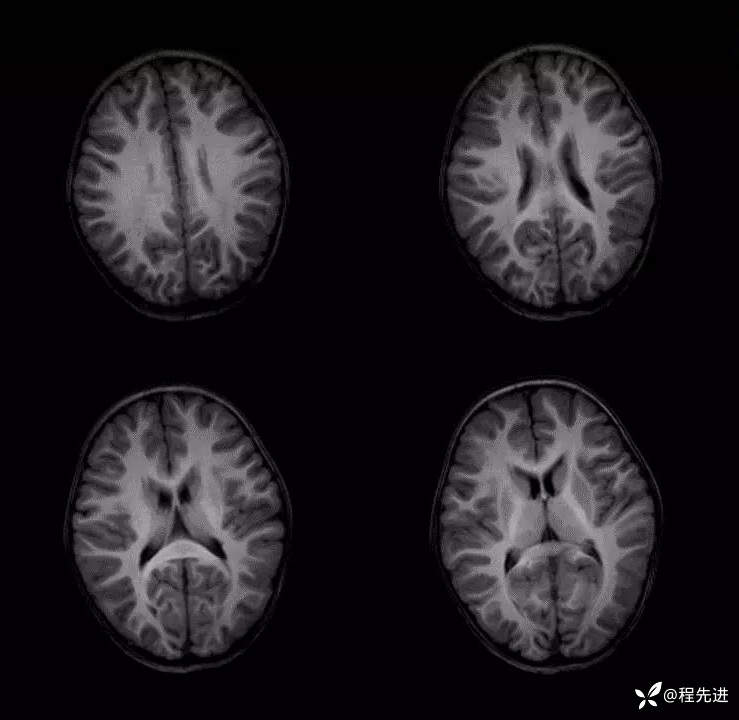

患者性别:女

患者年龄:3岁

主诉:间断呕吐2天,伴腹泻1天,惊厥1次

现病史:2天前进食后呕吐,非喷射状,1天前出现腹泻,每日4-5次。入院2小时前出现抽搐发作

辅助检查:便常规轮状病毒(+)

伴可逆性胼胝体压部病变的轻度脑炎 (7)